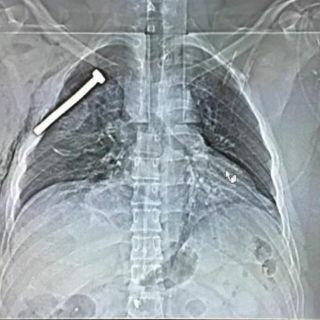

"El allanamiento en esa dirección permitió descubrir 15 kg de explosivo de tipo TATP [un explosivo altamente inestable], 150 litros de acetona, 30 litros de agua oxigenada, detonadores, una valija repleta de clavos y tornillos así como material destinado a confeccionar artefactos explosivos", dijo Van Leeuw.